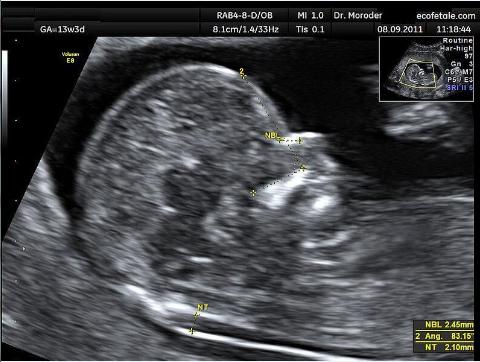

四、NT(颈后透明带扫描)检查注意事项

1.时间孕11-13.6周,需要提前预约(最好在孕11周之前)。

2.它是B超检查,不需要空腹,不需要憋尿。